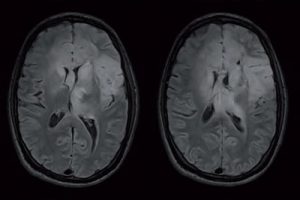

L'imagerie par résonance magnétique (IRM) est l'examen de référence, plus sensible et spécifique que le scanner crânien pour les tumeurs cérébrales, les séquences T2 et Flair permettent d’évaluer au mieux l’extension de la tumeur et de l’œdème péri tumoral (envahie par les cellules tumorales le plus souvent). L'image caractéristique est une masse fixant le gadolinium (produit de contraste pour l'IRM) avec une nécrose centrale et un œdème péritumoral.